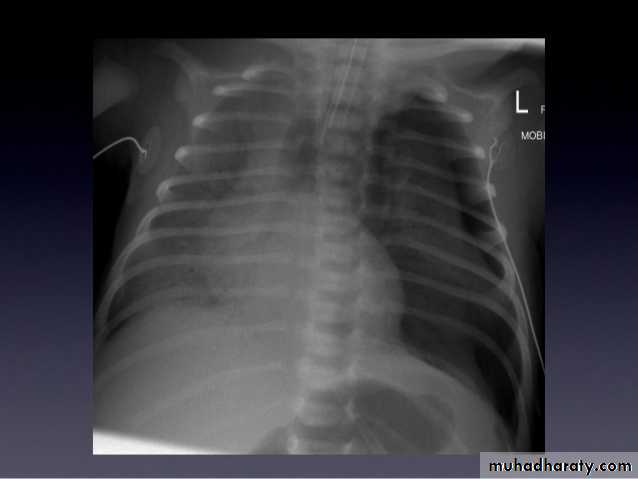

Total collapse total consolidation

Total collapse

48.opasified hemi thorax

49.total collapse